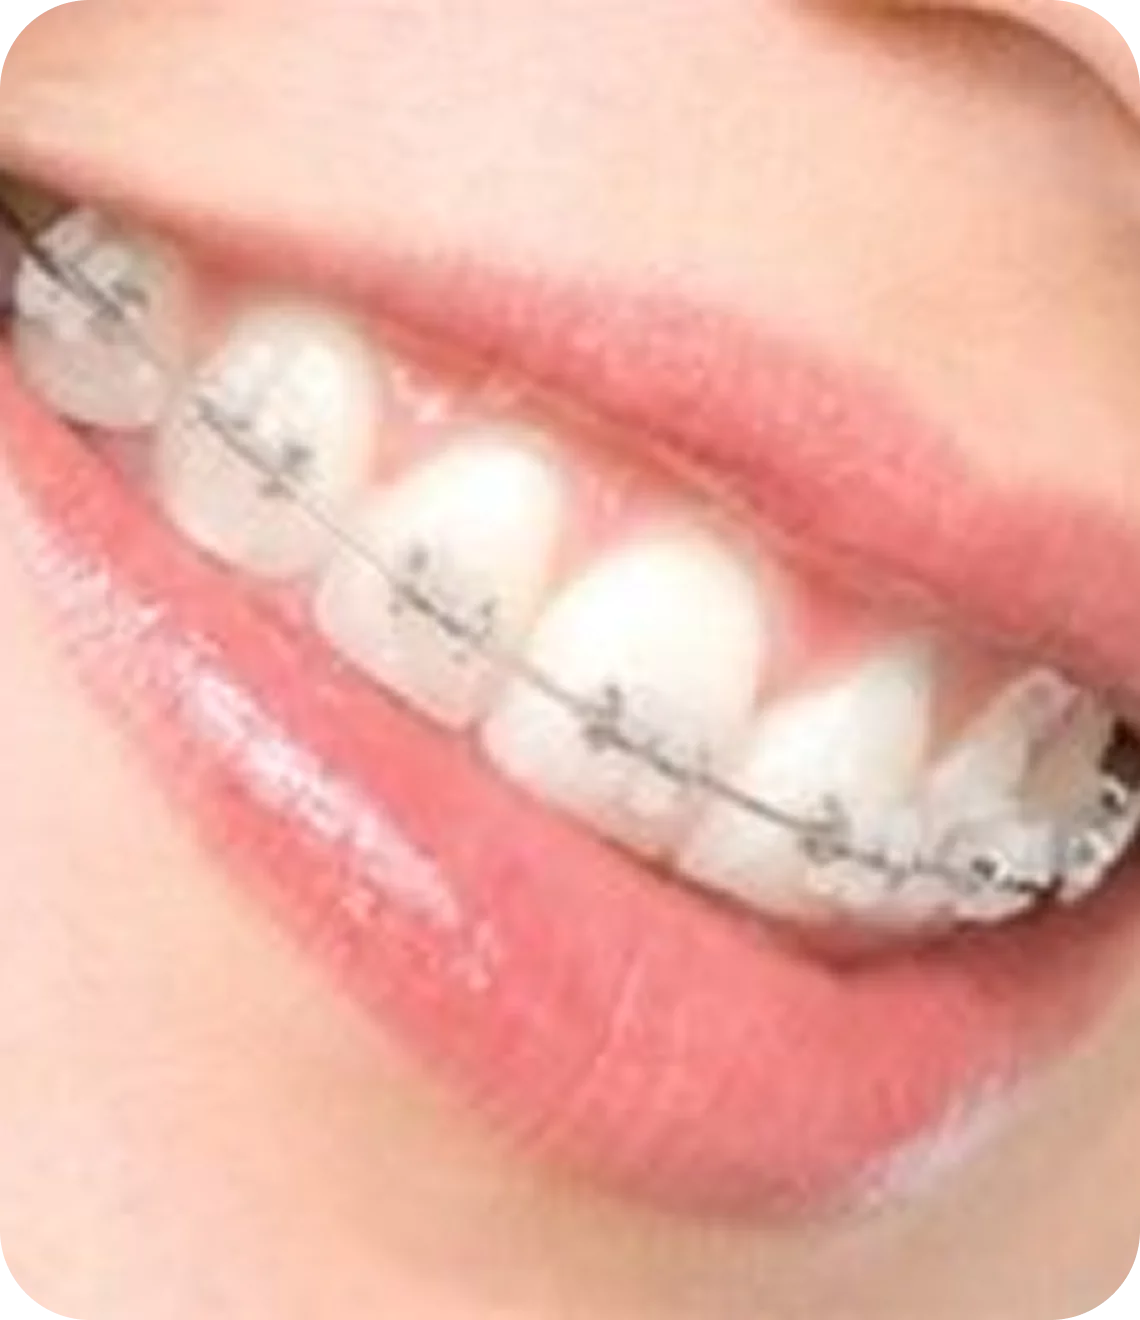

Braces

Fixed Braces

These are the braces, which are stuck onto the teeth with the help of chemicals. Broadly speaking, they are made up of steel or tooth-coloured ceramic. With the help of wire elastics, e-chains the teeth are pushed back. You might experience some discomfort and pain after the braces are placed. But with painkillers and time, patients get used to it. Fixed braces are used in cases where irregularity of teeth or malocclusion is more. Proper care should be taken in terms of brushing & cleaning of teeth regularly.

steel braces

The most common and recognizable braces are the stainless steel braces. These braces are very durable and different color ties may be used with them for decorative purposes to enhance the orthodontic experience.